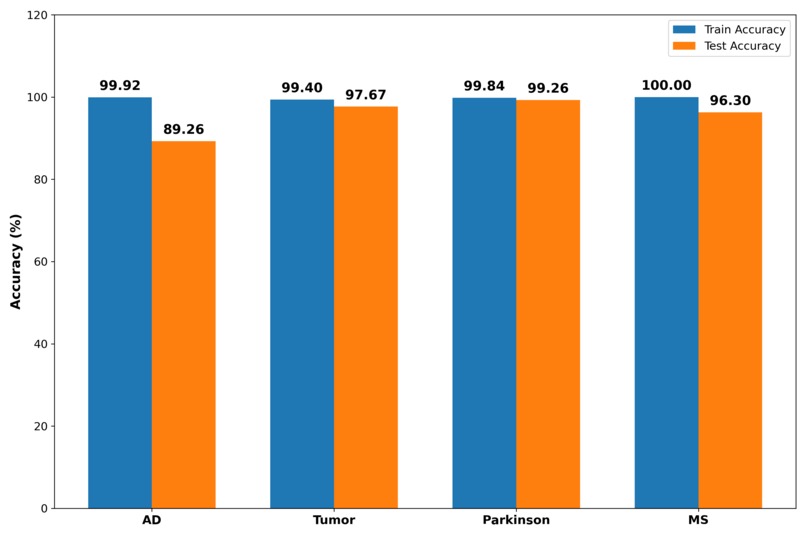

Cross-Domain Generalization Test Accuracy comparison Graph

- Achieved strong performance using minimal labeled data across multiple brain diseases

- Demonstrated that SSL representations generalize across neurological conditions

- Outperformed a fully supervised baseline in low-label settings